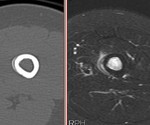

[画像診断]乳腺の硬化性腺症(sclerosing adenosis)について 2010-12-09